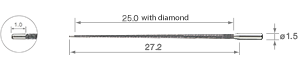

• Diamant-Beschichtung

• für Wurzelkanalerweiterung 32 mm

• Packung à 3 St.